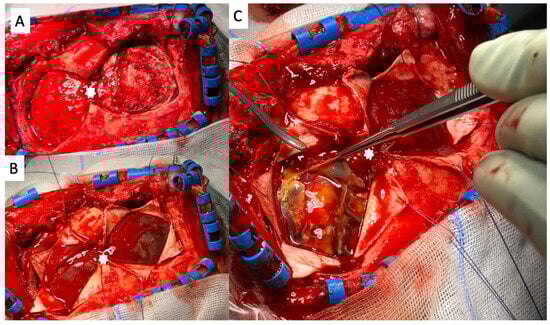

After the patient showed no clinical improvement, we identified an indication for revision surgery by means of craniotomy and hematoma evacuation, which was performed using the herein-introduced endless-loop craniotomy technique. Details of the surgical steps are displayed in the next section. Because of the vulnerable cortex and an already-present postoperative hemorrhage, we chose a non-watertight dura closure, and an epidural Jackson-Pratt drain was left for 2 days (Figure 1C,D). Figure 2 shows an illustration of the two different surgical techniques in a sagittal CT scout: burr-hole (A) and endless-loop craniotomy (B). The detailed operative steps for craniotomy, dura opening, and drain management are shown in Figure 3 and Figure 4. The operation was performed as planned without intraoperative complications.

Figure 4. An intraoperative view of the final steps of the endless-loop craniotomy procedure. (A): The dural lips were swiveled back to their original position. White asterisks mark the pre-existing position of the dura opening. (B): The dura mater was sutured using a continuous suture technique in a non-watertight fashion. (C): An epidural Jackson-Pratt drain was inserted to drain any residual hematoma, and the partial reinsertion of the bone flap was visualized. (D): The bone flap was partially reinserted, allowing for the closure of the craniotomy site.